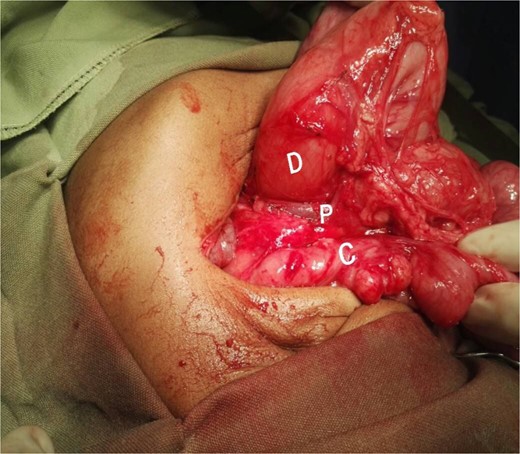

After optimization, a cholangiogram was performed through a limited right subcostal incision. The hypoplastic and shrunken gallbladder was cannulated, confirming the diagnosis of type III biliary atresia. During the Kasai portoenterostomy procedure, a PDPV was incidentally noted (Fig. 3). Although the PDPV did not cause any obstruction, the patient had no preoperative vomiting, and no obstruction was observed after injecting 30 ml of air via the nasogastric tube. The portoenterostomy was successfully completed, and the patient had an uneventful postoperative recovery. She has been referred for follow-up with the pediatric gastroenterology team for care and monitoring.

Interpretive view of biliary atresia case showing a PDPV crossing the second part of the dedendum. D, dedendum; L, liver; P, preduodenal portal vein.